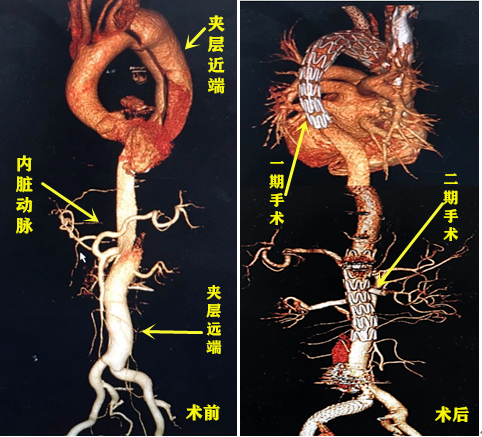

64岁的黄爷爷因为背部剧痛入院,没想到竟然是因为遭遇胸腹主动脉动脉夹层。一旦夹层撕裂,他很可能因为瞬间大出血猝死。幸运的是,近日,在历经两次微创手术后,成都市第三人民医院血管外科团队帮助黄爷爷完成了问题主动脉从上到下的修复。手术的成功开展,也开启了全省范围内微创方式治疗全段胸腹主动脉夹层的大门。

去年8月,黄爷爷突然感觉背部疼痛难忍,后经急诊绿色通道至成都市第三人民医院血管外科治疗。被诊断为“主动脉夹层”,CT提示动脉夹层撕裂严重。“从主动脉上端到末端均受夹层累及,并且多个重要内脏动脉同时受累。”对于黄爷爷的病情,成都市第三人民医院血管外科副主任医师崔驰用四个字进行了总结:命悬一线。如果不及时手术解决发生问题的血管,患者随时可能因主动脉夹层破裂大出血死亡。

为了保障患者的治疗安全,决定将手术分为两次进行。一期手术在去年8月22日顺利完成,通过植入主动脉的覆膜支架来帮助近端的血管破口“堵漏”。为避免黄爷爷在术后发生截瘫,团队为其制定了一个恢复周期,二期手术被安排于今年6月进行。

崔驰介绍说,在本次手术中用到的是目前血管外科最先进的“微创开窗技术”,即利用前沿3D打印技术结合患者术前CTA影像,制作出与患者主动脉形态完全吻合的“血管模具”。医生根据模具形态预先在支架上开凿小孔,并在术中通过血管将支架送入,再将小孔逐个精准对位于内脏动脉,即可完成内脏动脉重建和远端血管破口的封堵。手术伤口约2cm、术中出血量仅几十毫升,精准操作之下实现了患者的最大化受益。

手术的成功开展,也是填补了四川省微创手术治疗全段胸腹主动脉病变领域空白,对于大部分胸腹主动脉长段病变的患者来说,也是有了更多的选择。